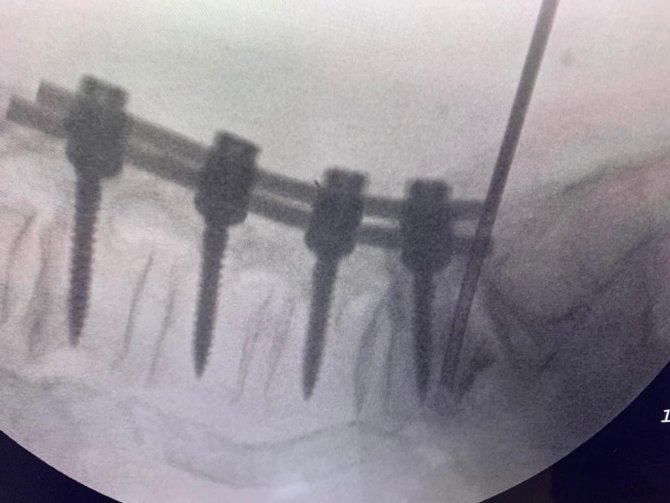

Hekimler; kırıklar, skolyoz eğrilikleri, tümörler, kanal daralması gibi ameliyatlarında vidalarla omurları desteklemede bulunuyor. Ancak vidaların bulunduğu omurlar düşme, çarpma gibi kazalar nedeniyle kırılabiliyor. Bu duruma müdahale etmek için ise açık ameliyat gerekiyor. Beyin ve Sinir Cerrahisi Uzmanı Prof. Dr. Kemal Yücesoy, vidalı omurganın kırığına dünyada ilk kez transforaminal transdiskal yaklaşımla sement desteği yaptı. Geliştirdiği yöntem, nöroşirürji alanında dünyanın en prestijli dergilerinden olan World Neurosurgery'nin son sayısında yayımlanarak literatüre girdi. Hastaların sadece 5 dakikasını alan ve 2 saat sonra günlük hayatına dönmesini sağlayan yöntem, Türkiye'ye gurur yaşattı.

Uzun süre, vidayı çıkarmadan kemik çimentosunu koyma konusunda çalışmalar yaptığını belirten Prof. Dr. Yücesoy, "Kapalı bel fıtığı ameliyatlarında iğneyle sinirin altına girerek izlediğimiz bir yol var. "Hastaların kemiğinin içine bu yoldan girilebilir" diye düşündüm ve bunu da uygulamaya başladım. Bu yöntemde, hastaya lokal anestezi uyguluyoruz. Kıkırdağın olduğu bölümden diskin içine iğneyle girip oradan da kemiğin içine ulaşıyoruz ve çimentoyu koyuyoruz. Bu daha önce hiç uygulanmamış bir yol. Kırılmış vidalı bir kemiğe ilk kez o vidayı çıkarmadan kapalı yöntemle girip müdahale etmiş olduk" diye konuştu.